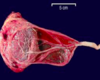

Physiology of lactation during pregnancy?

- Progesterone influences growth in size of alveoli and lobes of breast tissue

- Estrogen stimulates the milk duct system to grow and differentiate

- Prolactin causes differentiation of the alveoli and ductal structures

- Human placental lactogen (HPL) produced by the placenta, and causes breast, nipple, areola to grow

What are the benefits of breast feeding for the infant?

- Passive immunity: fully functional IgA, IgG and IgM passed from mom to baby, preventing infections, and starting baby off on good foot

-

Nutrition: formula-fed have higher, faster weight gain in newborn period and INC # of fat cells (these never go away)

1. Protects against obesity - Protects against allergies/asthma

- Bonding: helps produce confident infant and child